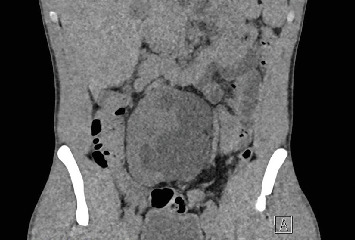

肾盂输尿管连接处梗阻(UPJO)见于约30%的异位肾患者。由于狭窄的骨盆空间和损伤异常结构的风险,异位盆腔肾UPJO提出了一个独特的治疗挑战。大多数使用机器人手术系统治疗盆腔异位肾UPJO的经验是基于儿科人群的。只有少数案例成功的机器人辅助手术在成人患者与这种情况已被描述。本病例报告表明,机器人辅助UPJO手术的适应症可以安全地扩展到包括骨盆异位肾的复杂成人病例。

Ureteropelvic junction obstruction (UPJO) is observed in approximately 30% of patients with ectopic kidneys. Due to the narrow pelvic space and risk of injuring aberrant structures, an ectopic pelvic kidney with UPJO presents a unique treatment challenge. Most experiences in treating UPJO in pelvic ectopic kidneys using robotic surgical systems are based on the pediatric population. Only a few cases of successful robotic-assisted surgery in adult patients with this condition have been described. This case reports illustrates that the indications for robotic-assisted surgery for UPJO may safely be expanded to include complex adult cases with pelvic ectopic kidney.